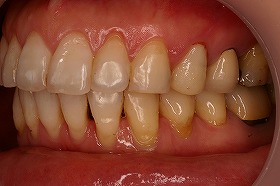

ガタガタの歯並びだと歯と歯のすき間に

ハミガキが行き届かず歯石が残り易くなります。

その歯石が虫歯や歯槽膿漏などの原因となり、

歯に悪影響を及ぼすのです。

この患者様は、非抜歯で矯正治療を進めることができ、

治療後は上下の噛み合わせもよくなりました。